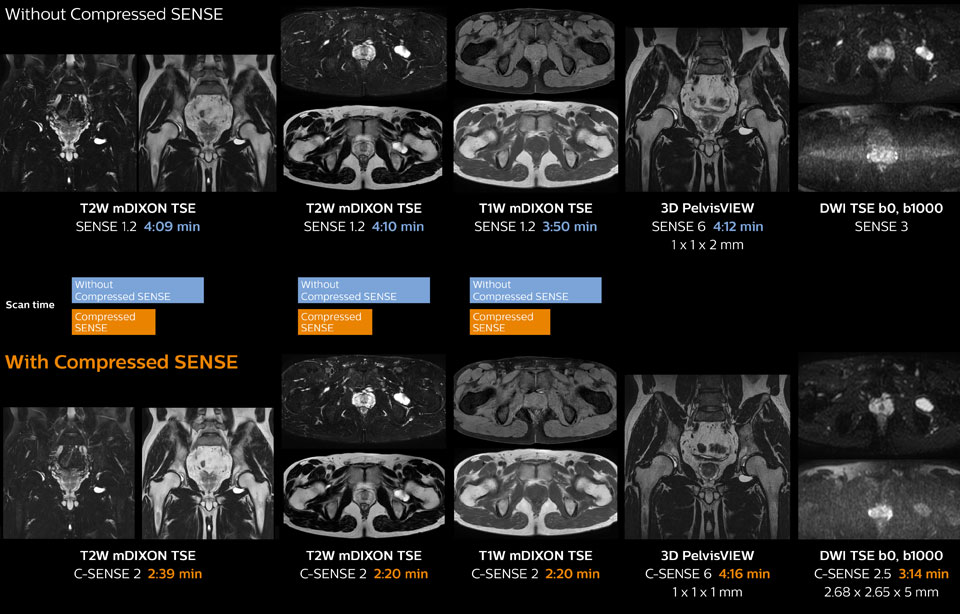

Hip with synovial cyst w/wo Compressed SENSE

Ingenia 1.5T MRI scans with and without Compressed SENSE are compared for this case of a hip with a synovial cyst. In the mDIXON sequence, the Compressed SENSE factor used is higher than the SENSE factor on the previous scan, so scan times are reduced without sacrificing image quality. The high resolution images are useful for diagnosing of a detailed dissection. The diffusion TSE with Compressed SENSE shows reduced noise compared to the Diffusion TSE with SENSE and the artifact has disappeared.

So in this case, Compressed SENSE helped in reducing scan times of the examination. The Compressed SENSE images allowed the radiologist to confidently diagnose the lesion and see the anatomic relationships of the abnormal signal to the surrounding structures.